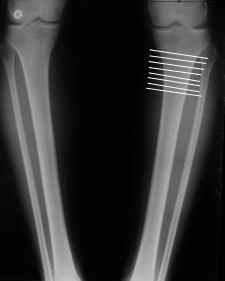

Вот ещё картинки, которые отправлял в Ортопод. Коррекция кривизны и удлинение на 3 см.

Сложно только цеплять короткий фрагмент, особенно когда удлинение. Спускался ниже - 5-7 см ниже сустава - тоже всё хорошо. Ниже уже бессмысленно - диафиз, ломать труднее, срастается дольше.

4. Если внимательно посмотришь на рентгенограммы, то в зоне перелома малоберцовой кости она втягиваетсмя внутрь, таким образом немного уменьшая объем тканей по внутреннему контуру. Причем чем выше - тем эффектнее. Не надо только совсем высоко лезть - там перонеус. Многих пайциенток это тоже смущает. Так что решаем проблему комплексно. На это, кстати, особо упирает Казбек Кудзаев.